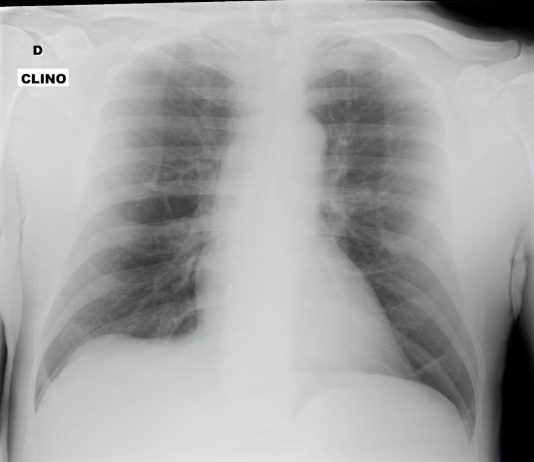

70 year-old male patient presented to the ED with fever...